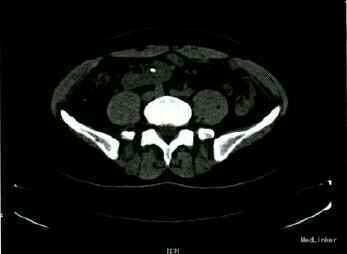

查体:腹平,未见胃肠型,腹软,全腹无压痛及反跳痛,右下腹可扪及一大小7cm×6cm的包块,质硬,无压痛,活动度可,表面皮肤未见异常,双肾区无叩击痛。门诊查血常规:正常。尿常规:隐血2+,白细胞+。泌尿系B超示:左侧异位肾,左肾结石,左肾积水。人院后行CTU+CTA示:左侧异位肾(位于右碰盆腔)及左肾结石,结石长径约1cm。

异位肾为肾脏先天性异常发育,盆腔异位肾常有形态上的改变,大部分较正常肾脏小。表面可呈分叶状,常伴有转位不全,肾盂向前,输尿管可异常缩短,。肾动脉发源在主动脉分叉上方或由其它分支发出,且常伴有其他复合畸形,部分可呈囊性变。较正常肾脏而言,异位肾更易罹患尿路结石及肾盂积水,病因主要是因为肾脏位置异常或旋转不良引起输尿管高位开口或迷走血管压迫上段输尿管或肾大盏引起梗阻。主要表现为腹痛、腰痛、血尿等,由于肾脏位置不同、疼痛性质难以判断,可能被误诊为阑尾炎、胆囊炎,女性还可能被误诊为盆腔附件炎。B超是首选的检查方法,具有经济、简单、安全、可重复、不受肾功能损害影响等优点,但容易造成误诊。CT能更好显示异位肾的位置及其与其他器官的结构关系,明确关系做最好。